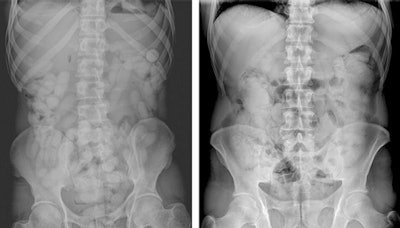

Abdominal x-ray images of packages that contain narcotic materials in solid and liquid forms. Left: A 34-year-old male body packer. In the intestinal lumens, multiple dense packages consisting of powdered cocaine with a scattered formation and ovoid morphology are observed. Right: A 48-year-old male body packer. In the colonic loops, widespread density increments with obscure contours and subtle serpiginous lucencies are observed. Be aware of the fact that contrary to solid drug-containing packages, these types of packages that contain cocaine in liquid form cannot be clearly distinguished. Image courtesy of BJR (April 2016, Vol. 89: 1060, pp. 20150888).In a single trip, a body packer can carry between 50 and100 packages, each containing 8 g to10 g of narcotic agents and weighing up to 1 kg in total. Body pushers, on the other hand, typically carry large packets in the rectum and/or vagina. The packets can usually be detected by physical examination without any need for imaging, but body pushers may also be packers at the same time. A third group known as body stuffers generally possess drugs either for their own use or for dealing on the street. Typically, they hide packets quickly when they encounter the authorities to avoid arrest. Cartels may use children or pregnant women in this capacity.